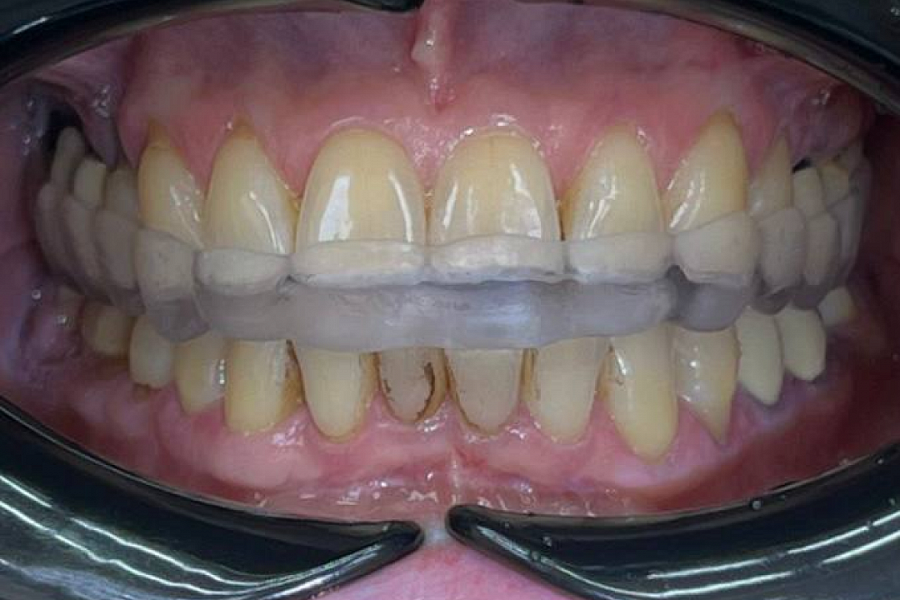

Сделали ортотик, чтобы поставить челюсть в правильное положение.

Далее по плану санация зубов и протезирование в правильной терапевтической позиции ВНЧС. С помощью виниров и коронок будет проведена эстетическая и функциональная реабилитация, получена красивая улыбка и качественное жевание. Лицо подтянется и помолодеет!!

Результат лечения